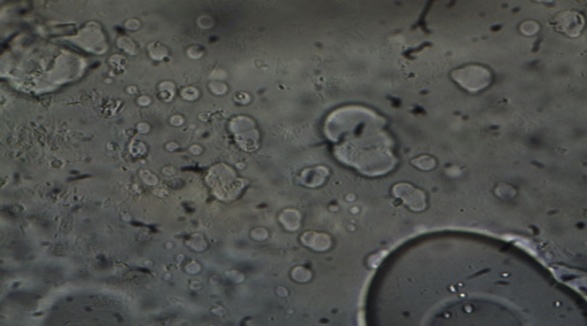

The optimized niosomal suspension (NF2) was observed under abinocular microscope. The fully formed niosome vesicles were visible and the image is as shown in fig.4.

Fig.1: Microscopic image of Niosomes under binocular microscope